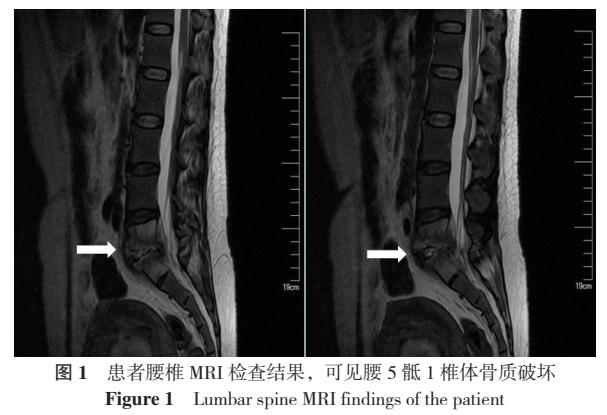

实验室检查:红细胞沉降率、C反应蛋白升高,白细胞计数及降钙素原正常。影像学检查:腰椎MRI平扫,腰5、骶1椎体及部分附件、椎体后方硬膜外异常信号(图1),考虑感染性病变可能。PET-CT检查:腰5骶1椎体上下缘代谢增高伴骨质破坏,腹盆腔多个轻度高代谢淋巴结,考虑椎间盘炎伴淋巴结炎症。子宫体积增大、壁增厚、内膜不均匀、代谢增高,考虑为刮宫术后改变伴感染可能,子宫壁内节育器影。